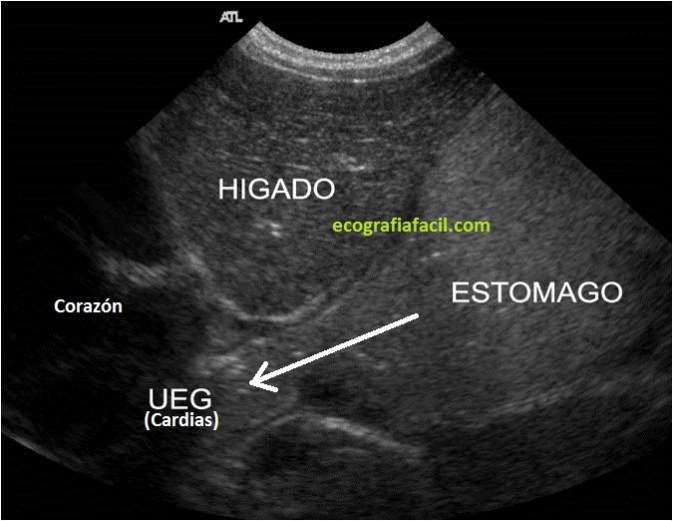

- LOCALIZAREMOS UNIÓN ESÓFAGO-GÁSTRICA, buscando el teórico lugar donde se localice el Cardias CON UN CORTE PARASAGITAL donde veamos la parte final del esófago en Longitudinal Y PERMANECEREMOS INMÓVILES DURANTE 10 MINUTOS, si durante ese tiempo se produce paso del estómago al esófago MÁS DE 3 ocasiones EN 10 MINUTOS, ES POSITIVO.

Esta es la imagen que debemos conseguir. La flecha indica la salida que busca el contenido gástrico del estómago, como se ve en la imagen donde el Cardias está abierto y se está produciendo el episodio de reflujo.

This is the image we should get. The arrow indicates the exit that seeks the gastric content of the stomach, as seen in the image where Cardias is open and the episode of reflux is occurring.